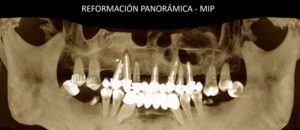

127 – Cirugía guiada en implantología

Paciente masculino, 54 años es referido al Instituto de Diagnóstico Maxilofacial para planificación de cirugía guiada con el objetivo de colocar implantes dentales en el